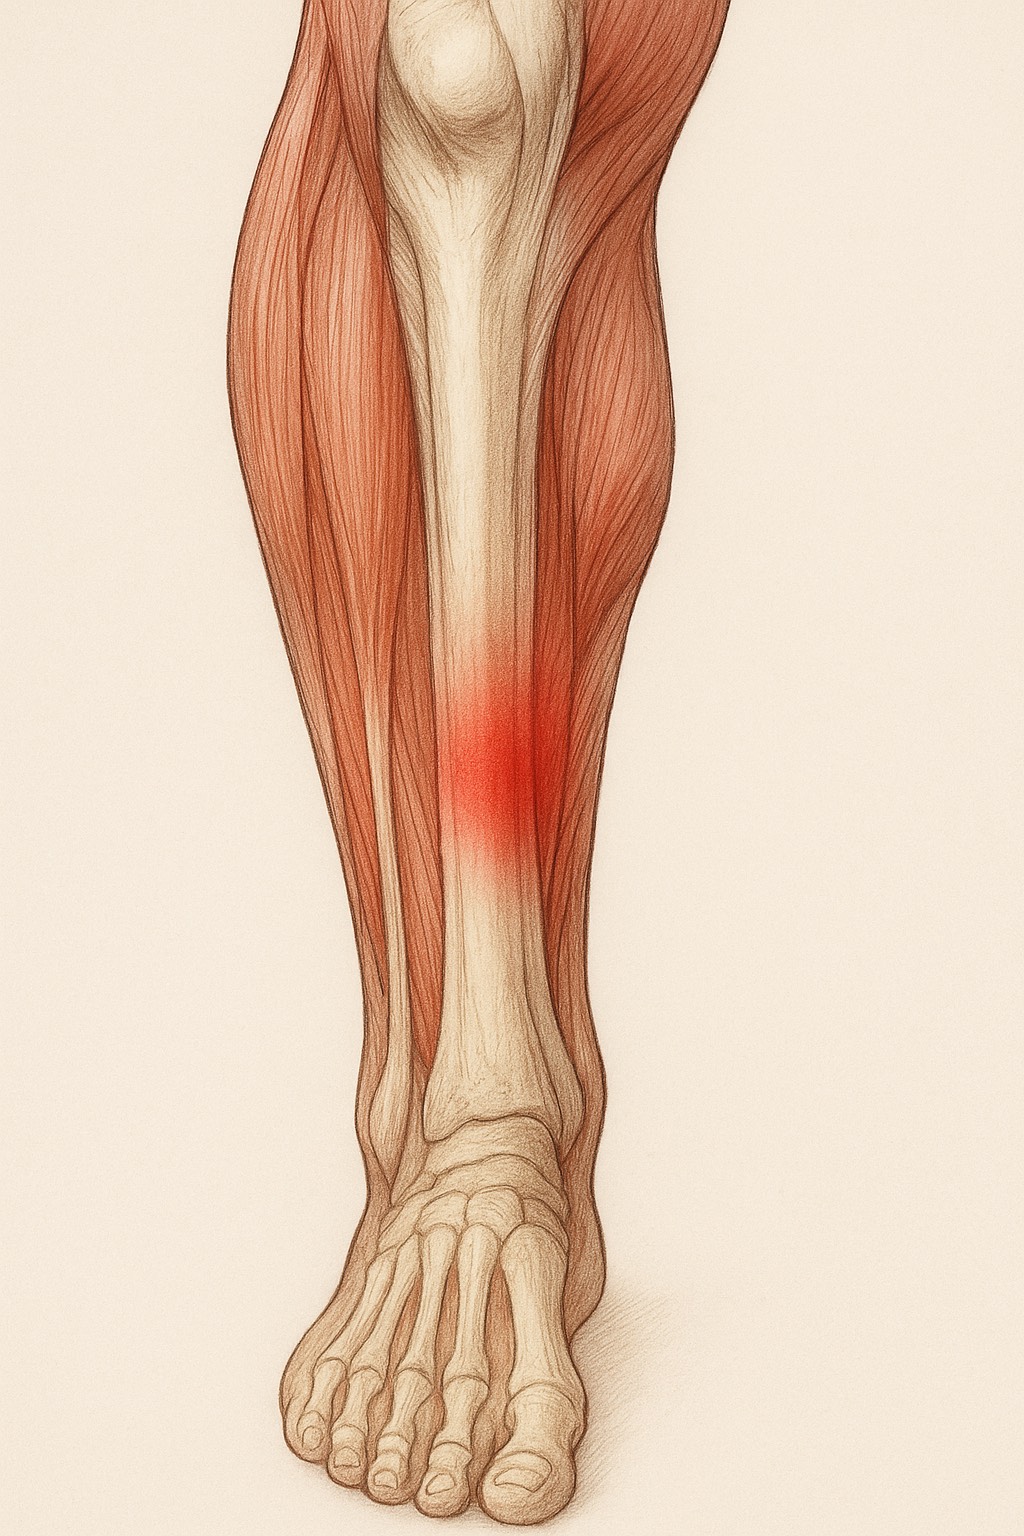

痛みが出やすい場所

アキレス腱の炎症は主に2つの部位に分けられます。

1.アキレス腱の中央部(腱の真ん中あたり)

・ふくらはぎと踵のちょうど間、腱の途中に炎症が起きるタイプ

・ランニングやジャンプの繰り返しで起こりやすい

・押すと硬くしこりのように感じることもある

2.アキレス腱付着部(かかとの骨に近い部分)

・踵の少し上、腱が骨にくっつく部分に炎症が出るタイプ

・シューズのかかとが当たって痛むことも多い

・骨の出っ張り(骨化や隆起)が伴う場合もある